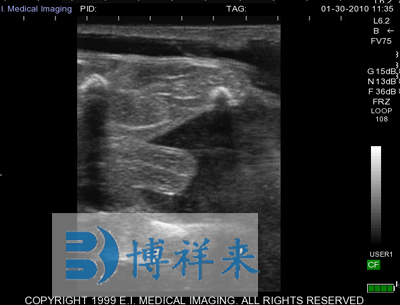

使用对象:牛、马等动物

| 尺寸和重量 | Ibex Lite:IP56 -黄色;8.9”L,7”W,2.2”D;3.61磅(1.63Kg) | 应用范围 | 牛,马,宠物,猪,珍惜动物和小反刍动物等 |

可换探头,可配备:128振元(5-8MHZ)直肠探头、128振元凸阵(2.5-5MHZ)直肠探头、128振元微凸探头以及特殊探头、支持3.5兆赫至7.5 MHz扇形探头等 支持用户可选择探头扫描方向 |

距离测量 连续的周长测量 网格测量选项(快速测量) 计算表 屏幕上的文本注释和箭头 |